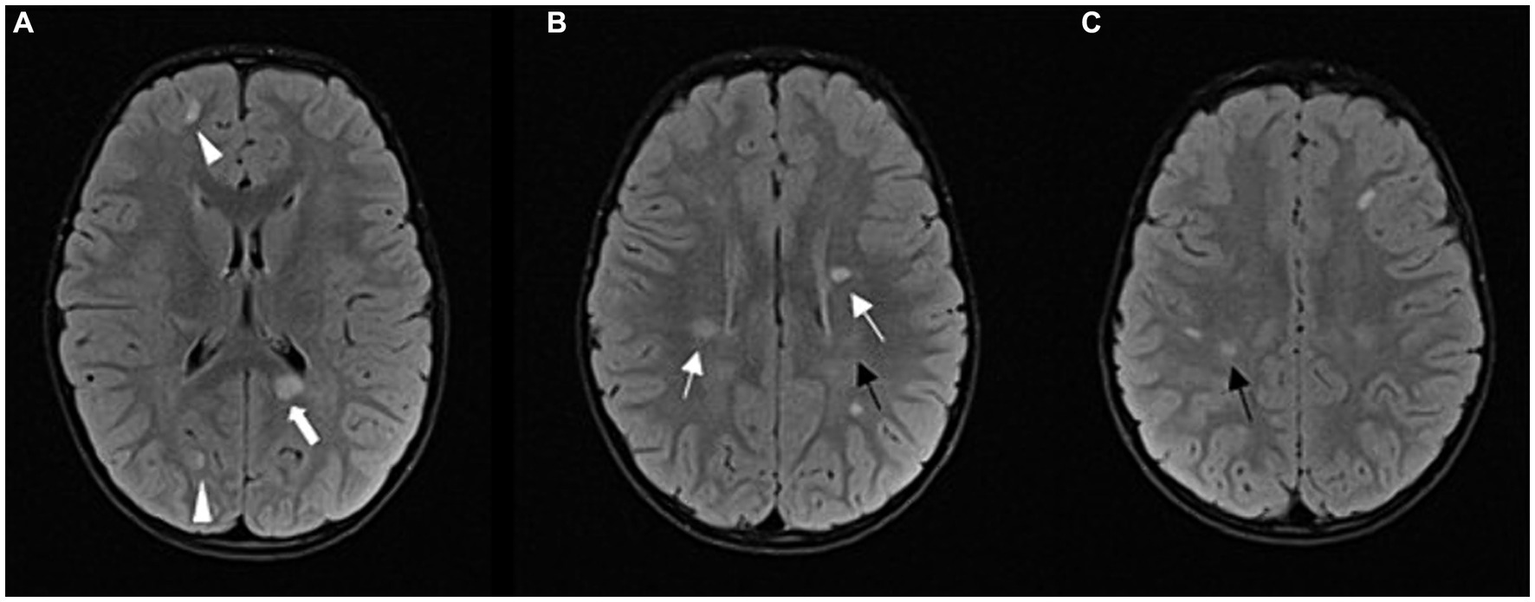

Figure 2

Follow-up MRI after 1 year: FLAIR sequence in axial plane at three different levels (A–C); progression of the disease; multiple demyelinating lesions in typical periventricular (arrows) and juxtacortical locations (arrowheads). Among the periventricular lesions, we can observe a lesion in the splenium of the corpus callosum on the left side (thick arrow). Other new lesions can also be observed in the subcortical and deep white matter of the frontoparietal lobes. The lesions shown in Figure 1 have partially regressed (black arrows).

Seven months after the second clinical event, follow-up MRI of the brain and spinal cord showed multiple new demyelinating infratentorial lesions. Given that he had two clinical events and dissemination in time and space on several follow-up MRIs, he met the 2017 McDonald’s criteria. Eighteen months after the first clinical episode, after a thorough discussion with the patient’s parents, we decided to start rituximab therapy. Before starting rituximab, we performed several laboratory tests – complete blood count with differential, lymphocyte subpopulations, liver and kidney function tests, hepatitis B, C and HIV screening, immunoglobulin levels, tuberculosis tests, VZV serology. Once the safety of this drug for the patient was assured, treatment with rituximab was started, using 500 mg per meter squared of body surface (maximum dose of 1,000 mg per dose), dosed on days 1 and 15, and then every 6 months (14). A follow-up MRI 6 months after rituximab administration showed regression of the multiple demyelinating lesions and no new lesions (Figure 3).